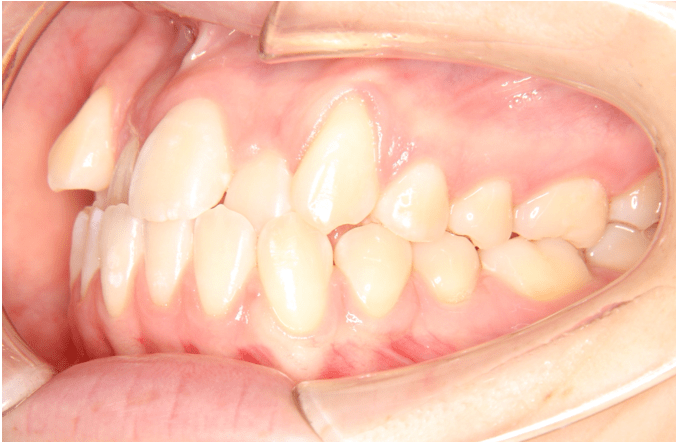

受け口とは、上下の歯の噛み方が逆になっている状態のことを言います。本来、上の歯が下の歯を覆う形で咬合していますが、受け口は下の歯が前にある状態のことです。

受け口は上下の顎骨の位置が、下顎が前に位置している「骨格性(こっかくせい)」のものと、歯の生え方によって下顎が前方に移動させないと噛むことができない「歯性(しせい)」のものがあります。

歯性の場合、下顎が前方にでる原因となっている歯の噛み合わせを変えることで下顎の位置が下がり、良好な顎の関係を得ることができます。